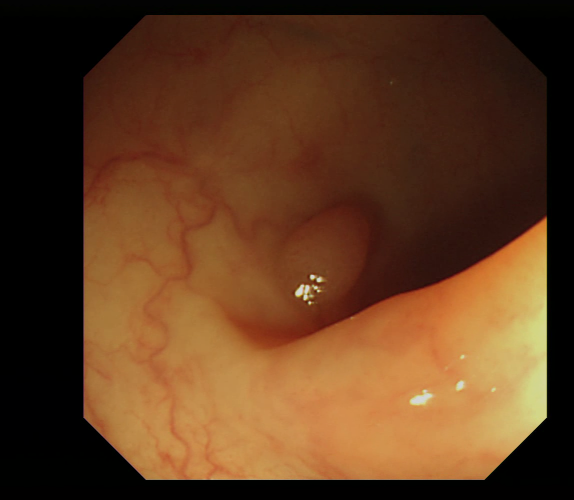

Colorectal cancer is the third most common cancer-related death in the United States in both men and women. According to the annual report provided by American cancer society [3], approximately 101,420 new cases of colon cancer and 44,180 new cases of rectal cancer will be diagnosed in 2019. Additionally, 51,020 patients are expected to die from colorectal cancer during 2019 in the United States. Most colorectal cancers start as benign polyps in the inner linings of the colon or rectum. Removal of these polyps can decrease the risk of developing cancer. Colonoscopy is the gold standard for screening and detecting polyps [5]. Screening and analysis of polyps in colonoscopy images is dependent on experienced endoscopists [21]. Polyp detection is considered as a challenging task due to the variations in size and shape of polyps among different patients. This is illustrated in Fig. 1, where the segmented regions vary in size, shape and position.

Refer to caption

Figure 1: Some examples of polyps from colonoscopy images (first row) and their corresponding manual segmentations provided by expert endoscopists (second row).